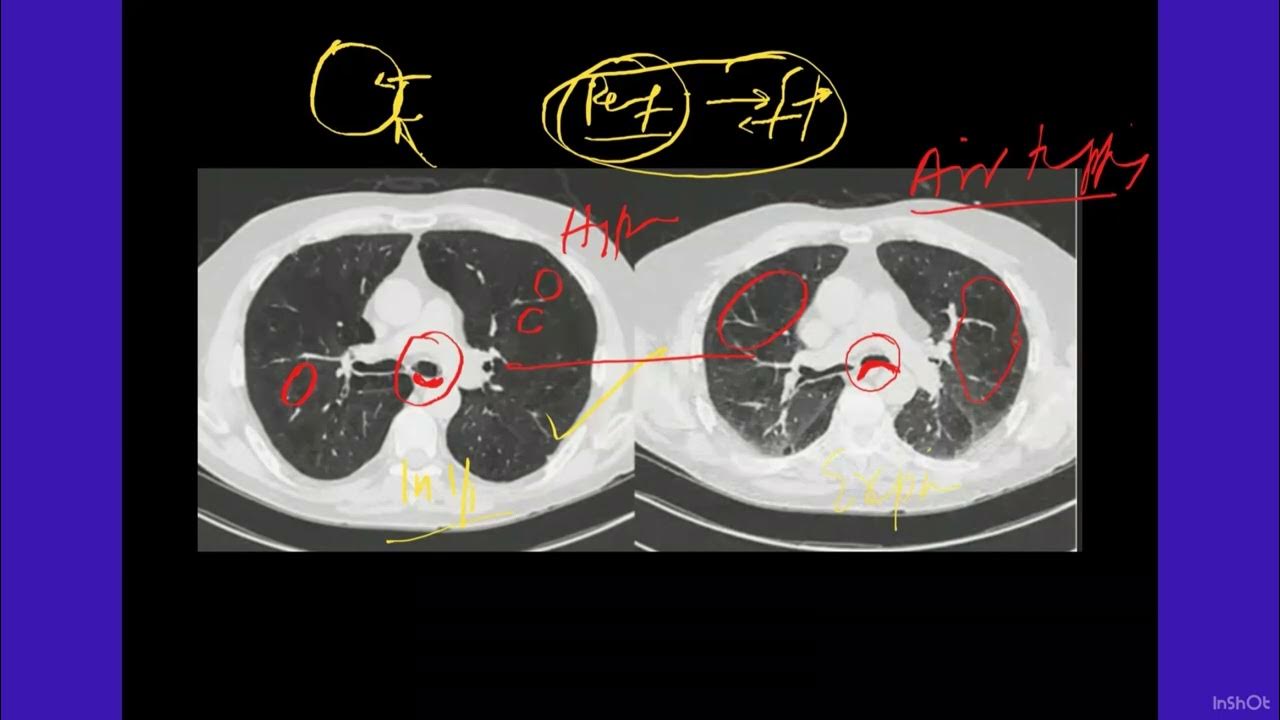

Mosaic Attenuation In Lungs Made Simple YouTube

Tkr htp 02 CRAZY PAVING PATTERN VS MOSAIC ATTENUATION IN EASY WAY

Discrimination Between Ground Glass Opacities And Mosaic Attenuation In

Snippet 08 Mosaic Attenuation